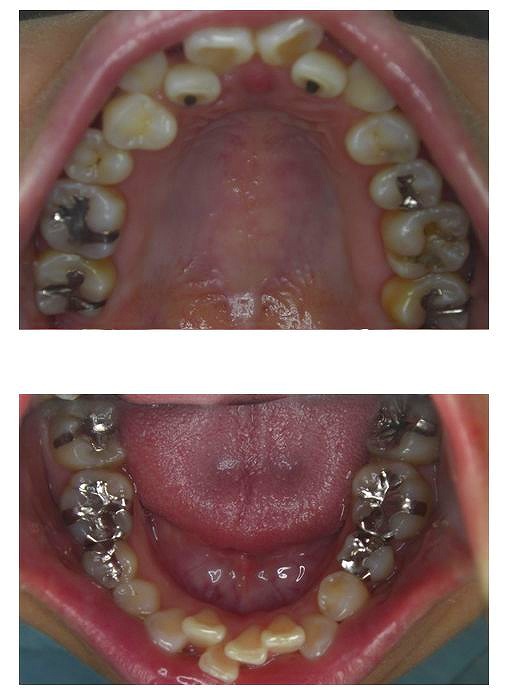

口の中を見ると、所々しか金属がはいってないようにみえます。

しかし、今回は症状もひどく、精神的にも悩まれた期間が長いようで、すべてセラミックのものと交換しました。

もちろん、セラミックですからアレルギーはありません。というわけで、お口の中から金属が消えて、心も晴れて歯も白くなりました。